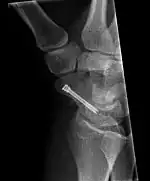

Scaphoid fracture before and after operation

Fractures of the scaphoid are the most common of the carpal bone injuries, because of its connections with the two rows of carpal bones.[1]:177

The scaphoid can be slow to heal because of the limited circulation to the bone. Fractures of the scaphoid must be recognized and treated quickly, as prompt treatment by immobilization or surgical fixation increases the likelihood of the bone healing in anatomic alignment, thus avoiding mal-union or non-union.[6] Delays may compromise healing. Failure of the fracture to heal ("non-union") will lead to post-traumatic osteoarthritis of the carpus.[1]:189 One reason for this is because of the "tenuous" blood supply to the proximal segment.[3] Even rapidly immobilized fractures may require surgical treatment, including use of a headless compression screw such as the Herbert screw to bind the two halves together.

Healing of the fracture with a non-anatomic deformity (frequently, a volar flexed "humpback") can also lead to post-traumatic arthritis. Non-unions can result in loss of blood supply to the proximal pole, which can result in avascular necrosis of the proximal segment.

Scaphoid fractures may be difficult to diagnose via plain x-ray. A repeat x-ray may be required at a later date, as might cross-sectional imaging via MRI or CT scan.[6]